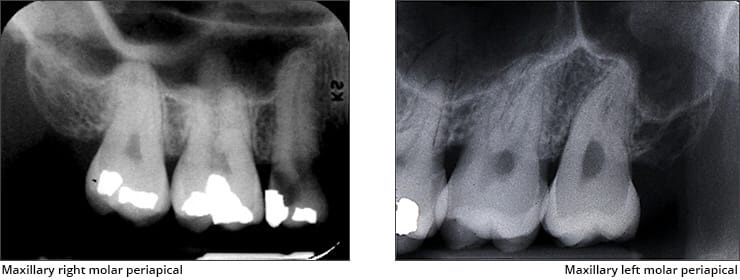

• Zygomatic bone – The zygomatic bone or cheek bone attaches to the right and left sides of the posterior maxilla. The zygomatic bone, quadrangular in shape, broadens as it extends posteriorly. This bilateral radiopaque structure is also known as the malar bone.

• Zygomatic process – Extension of lateral surface of maxilla. Radiopaque U-shaped structure.

• Maxillary tuberosity – Rounded bony prominence present posterior to third molar.

• Maxillary sinus – Largest paranasal sinus occupies entire body of maxilla. Pyramidal in shape. Superior wall forms floor of mouth.

• Coronoid process – It appears as triangular radiopacity with its apex divided & in the region of the third molar. Narrow in lateral dimension. The coronoid process is the only mandibular structure recorded on maxillary molar periapicals.